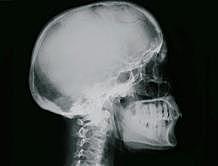

Rayos X

El físico alemán Wilhelm Conrad Röntgen descubrió los rayos X en 1895, mientras experimentaba con los tubos de Hittorff-Crookes y la bobina de Ruhmkorff para investigar la fluorescencia. Determinó que los rayos creaban una radiación muy penetrante, pero invisible, que atravesaba grandes espesores de papel e incluso metales poco densos. Los llamó "rayos incógnita", o "rayos X" porque no sabía qué eran, solo que eran generados por los rayos catódicos al chocar contra ciertos materiales